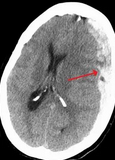

Subdural hematoma is a common presentation for elderly patients who have a fall. Surgical or medical interventions are based on the patient’s physical examination results, regardless of the size of the subdural collection or edema. Because this patient is clinically awake and oriented and the hemiparesis is mild, the correct approach is to delay treatment of the subdural hematoma until the patient develops symptoms or has evidence of recurrence.

The treatment for subdural hematoma consists of graded treatments based on clinical examination results during the course of the injury. Conservative treatment is favored for patients with normal or near-normal examination results such as this one. In patients with impaired consciousness, signs of uncus herniation, or significant focal neurological deficits, surgical evacuation is the treatment of choice. Initially, surgery entails a large craniotomy to remove the clotted hemorrhage. Over days to weeks, the hemorrhage begins to liquefy, which allows for more conservative surgical approaches such as burr hole evacuation or a subdural evacuation port system drain procedure to drain the collection slowly. Trying to get the patient to the point where the hemorrhage has liquefied before attempting surgery decreases morbidity. In patients who have recurrent hemorrhage or hemorrhage expansion, embolization of the middle meningeal artery via an endovascular approach has been shown to prevent further recurrence of hemorrhage. This patient has had only one hemorrhage and no expansion and so would not be a candidate for this approach. Prophylactic intubation and mechanical ventilation are not warranted in this patient who has no respiratory distress and for whom emergency surgery is not planned.12